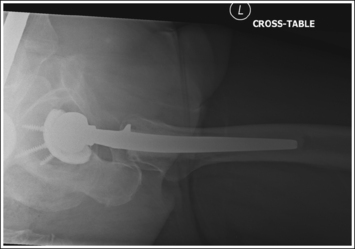

See Figure 7-15 and Box 7-4.

Scatter radiation is controlled. The proximal femur demonstrates uniform density across it.

• Tight collimation and placement of a flat lead contact strip or the straight edge of a lead apron over the top, unused half of the IR, as shown in Figure 7-16, also prevent scatter radiation from reaching the IR.

• Compensating filter. Frequently, when an exposure (mAs) is set that adequately demonstrates the hip joint, the proximal femur is overexposed because of the difference in body thickness in these two regions. A wedge-type compensating filter attached to the x-ray tube can be used to obtain uniform image density of the hip joint and proximal femur. Align the thin end of the filter with the femoral neck and the thicker end with the proximal femur.

The femoral neck is demonstrated without foreshortening. The proximal aspects of the greater and lesser trochanters are demonstrated at approximately the same transverse level.

• An axiolateral projection of the hip is obtained by placing the patient on the imaging table in an AP projection, with the unaffected hip positioned next to the lateral edge of the table. Flex the patient's unaffected leg until the femur is as close to a vertical position as the patient can tolerate, and then abduct the leg as far as the patient will allow. Support this leg position by using a specially designed leg holder or suitable support. Flexion and abduction of the unaffected leg move its bony and soft tissue structures away from the affected hip. Inadequate flexion or abduction of the unaffected leg results in superimposition of soft tissue onto the affected hip, preventing visualization of the affected hip (see Image 12).

• IR placement. Once the patient's unaffected leg has been positioned, place the grid IR against the patient's affected side at the level of the iliac crest (Figure 7-16). To demonstrate the affected femoral neck without foreshortening, align the x-ray tube horizontally with the central ray perpendicular to the femoral neck and adjust the distal end of the IR until the receptor's long axis is perpendicular to the central ray and parallel with the femoral neck.

• Localizing the femoral neck for central ray alignment. To localize the affected femoral neck, first find the center of an imaginary line drawn between the superior symphysis pubis and the ASIS. Then, bisect that line by drawing a perpendicular line distally (Figure 7-17). This imaginary line parallels the long axis of the femoral neck as long as the leg is not abducted. Once the long axis of the femoral neck has been located, align the central ray perpendicular to it and the IR parallel with it.

FIGURE 7-17 Locating the femoral neck and proper image receptor placement for small and average patients.

• Effect of central ray and femoral neck misalignment. Misalignment of the central ray with the femoral neck results in femoral neck foreshortening and a shift in the transverse level at which the greater trochanter is located. If the angle formed between the femur and the central ray is too large, the proximal greater trochanter is demonstrated proximal to the transverse level of the lesser trochanter and is superimposed by a portion of the femoral neck (see Image 13). If the angle between the femur and the central ray is too small, the proximal greater trochanter is demonstrated distal to the transverse level of the lesser trochanter. This mispositioning seldom occurs, because the imaging table and tube position prevent such a small angle.

The lesser trochanter is in profile posteriorly, and the greater trochanter is superimposed by the femoral shaft.

• Rotation of the patient's affected leg determines the relationship of the lesser and greater trochanter to the proximal femur on an axiolateral hip projection. In general, when a patient is placed on the imaging table and the affected leg is allowed to rotate freely, it is laterally (externally) rotated.

• Effect of leg rotation on proximal femur visualization. To position the proximal femur in a lateral projection (90 degrees from the AP projection), demonstrating the lesser trochanter in profile posteriorly and superimposing the greater trochanter by the femoral shaft, the affected leg must be internally rotated until an imaginary line drawn between the femoral epicondyles is positioned parallel with the imaging table. The patient's foot is angled internally 15 to 20 degrees from a vertical position (Figure 7-18). If the affected leg is not rotated internally, the greater trochanter is demonstrated posteriorly and the lesser trochanter is superimposed over the femoral shaft (see Image 14). How much greater trochanter is demonstrated without femoral shaft superimposition depends on the degree of external rotation. Greater external rotation increases the amount of greater trochanter shown.

IMAGE 14

• Positioning for a proximal femoral fracture or dislocation. When a patient has a dislocated hip or a suspected or known proximal femoral fracture, the leg should not be internally rotated, but left as is. Forced internal rotation of a dislocated hip or fractured proximal femur may injure the blood supply and nerves that surround the injured area. Because the patient's leg is not internally rotated in such cases, it is acceptable for the greater trochanter to be demonstrated posteriorly and the lesser trochanter to be superimposed over the femoral shaft (see Image 15).

IMAGE 15

The femoral neck is at the center of the exposure field. The acetabulum, femoral head and neck, greater and lesser trochanters, and ischial tuberosity are included within the collimated field. Any orthopedic apparatus should be included in its entirety.

• Center a perpendicular central ray to the patient's midthigh, at the level of the femoral neck, to place it in the center of the exposure field. The center of the femoral neck is located at a level 2.5 inches (6.25 cm) distal to the midpoint of a line connecting the ASIS and superior symphysis pubis. Open the longitudinal collimation the full length of the IR. Transversely collimate to within 0.5 inch (1.25 cm) of the proximal femoral skin line.

• A 10- × 12-inch (24- × 30-cm) IR placed lengthwise should be adequate to include all the required anatomic structures. A larger IR and lower centering point may be necessary to include hip orthopedic apparatus (Figure 7-19).

• IR placement alternative. The level at which the IR is placed along the patient's lateral body surface determines whether the acetabulum and femoral head are included on the IR. For patients with minimal lateral soft tissue thickness, the upper IR edge should be firmly placed in the crease formed at the patient's waist, just superior to the iliac crest (see Figure 7-17). For patients with ample lateral soft tissue thickness, the upper IR edge needs to be positioned superior to the iliac crest (Figure 7-20). This superior positioning will result in magnification because of the increase in the object–image receptor distance (OID) but is necessary if the acetabulum and femoral head are to be included on the axiolateral hip projection.